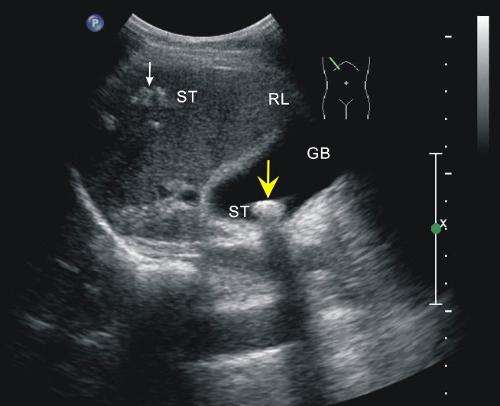

以右上腹部剧痛、高热,多见于胆道蛔虫病、肝脓肿、胆道结石等。持续右上腹钝痛考虑病毒性肝炎、原发性肝癌、慢性胆囊炎、肝脓肿等。

2、黄疸伴肝大